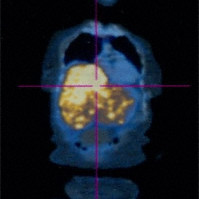

Metastatic choroidal melanoma

Metastatic choroidal melanoma - Total body PET:CT puts the form of spiral CT and the function seen with positron emission tomography on the same diagnostic page.